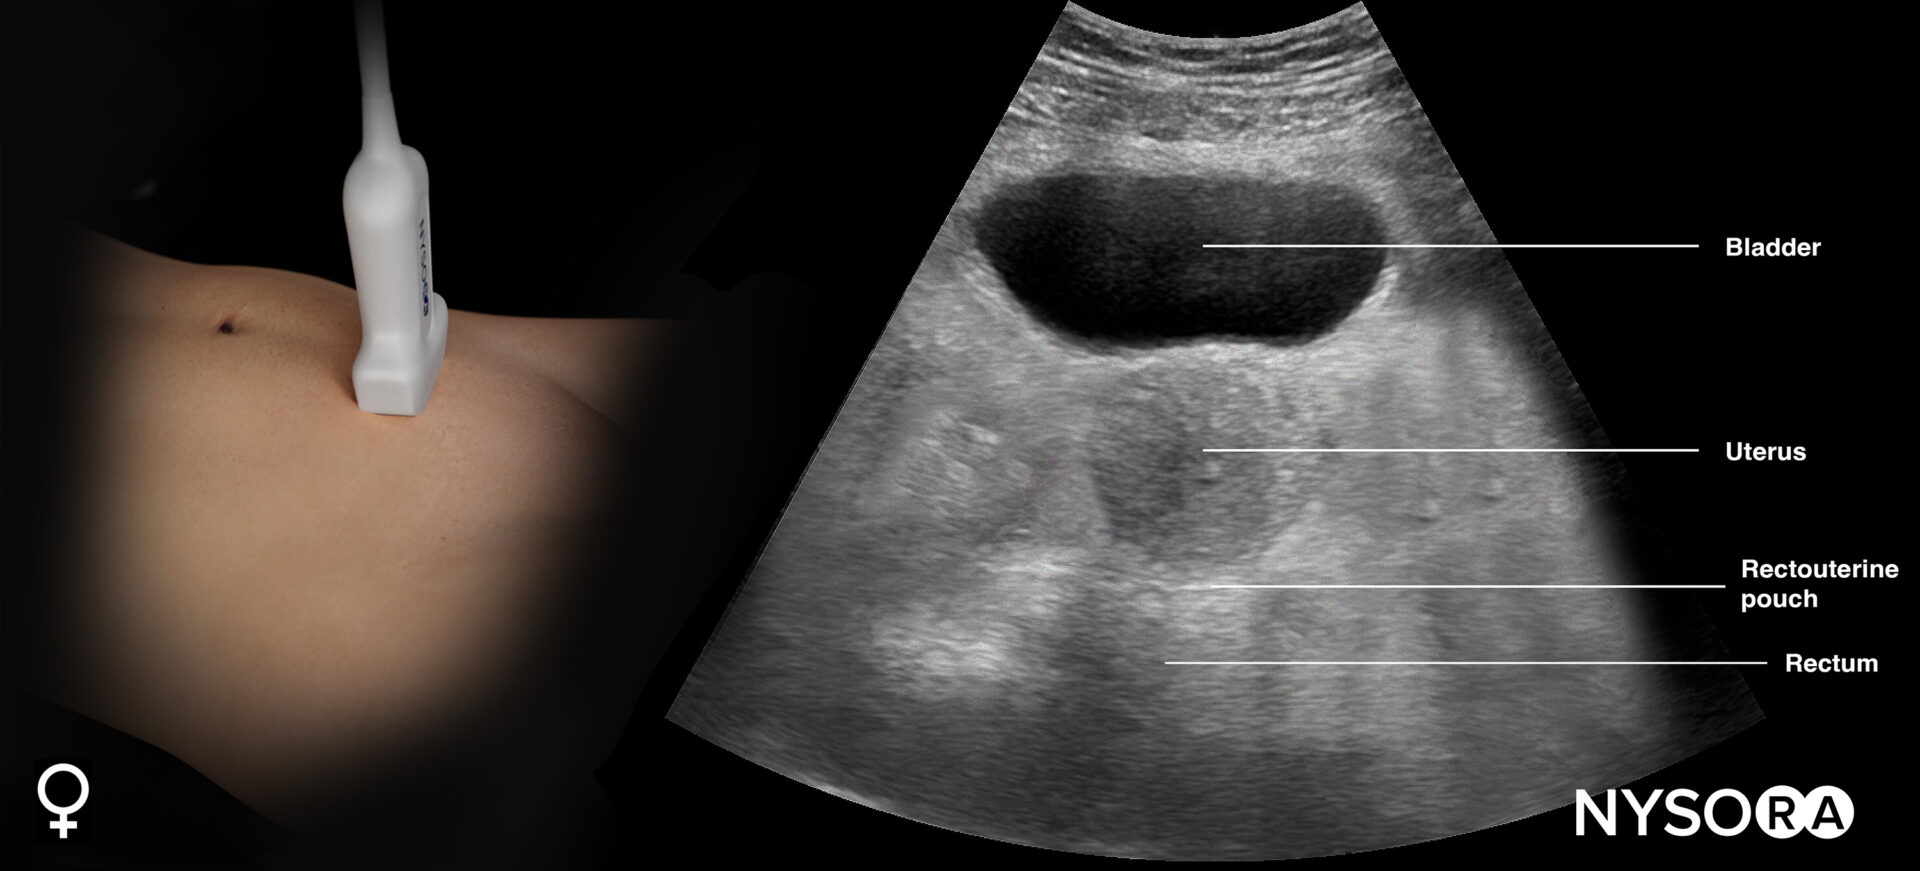

This view assesses the presence of free fluid in the pelvis.

- Position the transducer just above the pubic bone in the midline between the umbilicus and the pubic bone.

- The bladder can be used as an internal anatomical landmark to scan the area behind and lateral to the bladder for free fluid (the rectovesical pouch in men and the rectouterine pouch, or pouch of Douglas, in women).

- Step 2: Transverse view (orientation marker toward the patient’s right)

Sonoanatomy of interest in females:

Transducer position and ultrasound anatomy of the female pelvis.

Pelvic free fluid collects behind the bladder or the area lateral to the bladder (rectovesical pouch in men and the rectouterine pouch or pouch of Douglas in women).